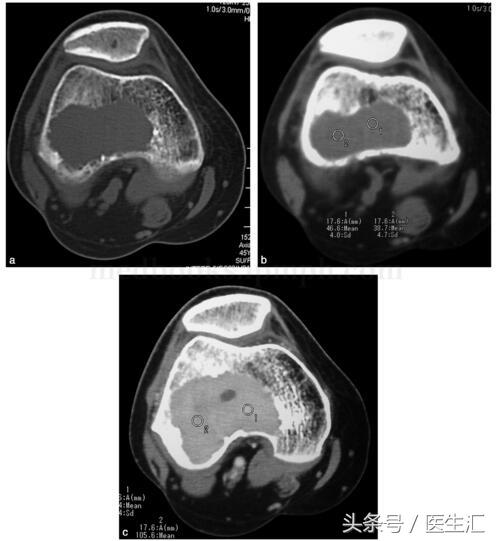

影像學檢查:X 線示右股骨遠端骨端發(fā)生的一個偏心、基質(zhì)均勻、皮質(zhì)膨脹、皮質(zhì)無骨破壞、無骨膜反應(yīng)、無軟組織腫塊的溶骨性破壞(圖29‐1a,圖29‐1b)。CT 示右股骨遠端骨端的溶骨性破壞,基質(zhì)均勻,注射造影劑后,病變強化,CT 值由強化前的40HU 增加到強化后的110HU(圖29‐2a~圖29‐2c)。

圖29‐2

a﹒CT 橫斷面示股骨外髁處溶骨性骨破壞(骨窗);

b﹒CT 橫斷面示股骨外髁處溶骨性破壞,CT 值為46HU(軟組織窗);

c﹒CT 橫斷面示增強CT 示腫瘤強化,CT 值達105HU